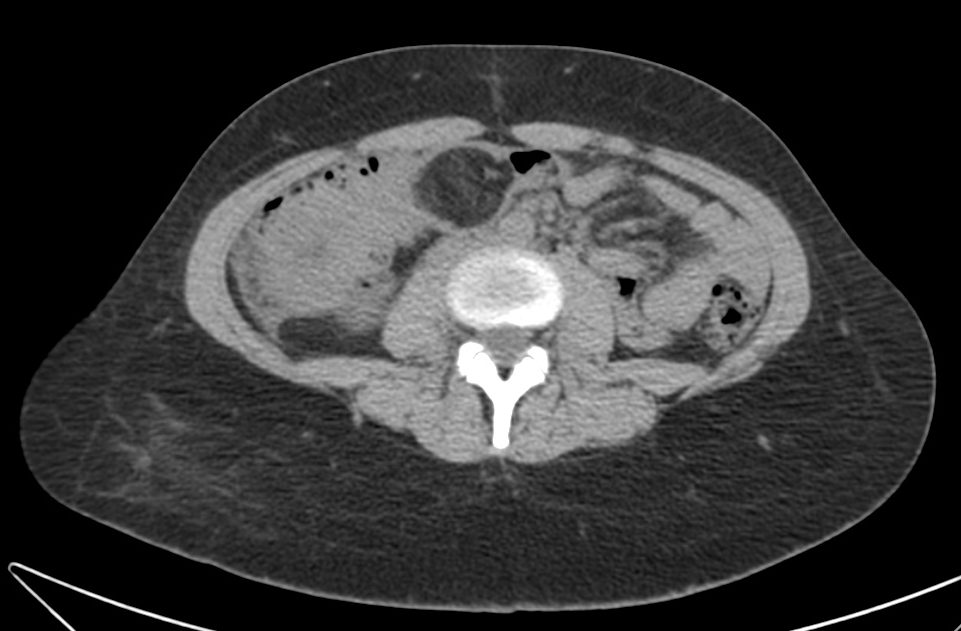

- CT abdominal: Es la prueba de elección.

- Masa con baja densidad intraluminal + patrón de burbujas de aire moteado ( patrón característico).

- Edema de pared y engrosamiento de mucosa.

- Obstrucción intestinal: cambios de calibre y dilatación de asas pre estenosis. El CT puede determinar la causa, localización y grado de obstrucción intstinal.

- El CT puede ayudar a distinguir entre un bezoar y particulas de comida. Los bezoares son redondos u ovoides, flotan en la superficie de agua/aire rodeados del contenido gástrico y que además muestran menor densidad que las partículas de comida. Los bezoares grandes tienden a rellenar todo el lumen y muestran burbujas distribuidas en el intersticio de la masa. Sin embargo, en ocasiones puede ser dificil difrenciar un bezoar de un cantidad considerable de comida retenida o de las heces si se localizan en el colon. Un hallazgo que puede ayudarnos, es identificar que dicha masa esta produciendo una obstrucción.

- La ventana estándar abdominal de (level, 40 H; width, 350 H) puede hacer muy dificil el diagnóstico de bezoar. Es recomendable bajar el Nivel/Level de la ventana hasta los L -1oo H o jugar con dichos niveles hasta identificar mejor las características del bezoar.